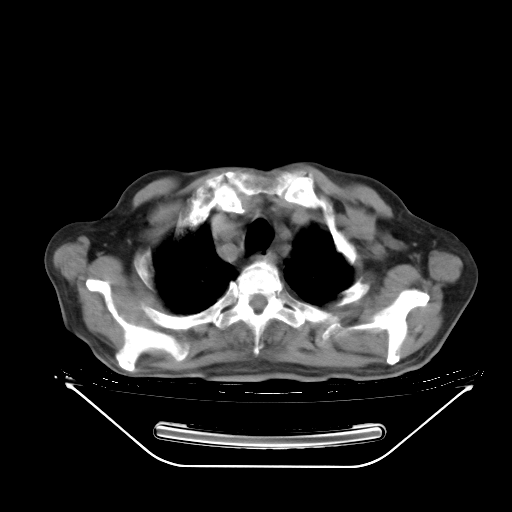

今天复查肺部CT,发现双肺广泛磨玻璃样改变。所以我把3月19日和5月9日相隔50天的肺部CT上传。请大家会诊。

2009年3月19日肺部CT片。

2009年3月19日肺部CT

5月9日肺部CT(在4月27日齐鲁医院肺部CT描述部分肺组织磨玻璃样改变,12天后肺组织广泛磨玻璃样改变)

2009年5月9日肺部CT

大致读了系列胸部CT:纵隔窗无明显异常,肺窗:从4、27至今:主要是双肺中下野外带可见毛玻璃样改变,目前处于急性肺泡炎阶段,至于原因考虑1、结替组织或胶原血管性疾病所致?2、恶性疾病如恶组在肺部所致的表现或细支气管肺泡癌?3、药物或其它原因如肺蛋白沉着症所致肺泡炎目前不太可能?总之,明天就去请我院的呼吸科、感染科、血液科和临免专家会诊哈。